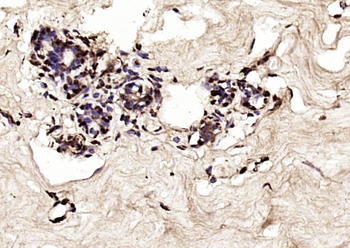

IF, IHC-Fr, IHC-P

应用稀释比例:IHC-P=1:100-500, IHC-F=1:100-500, IF=1:100-500